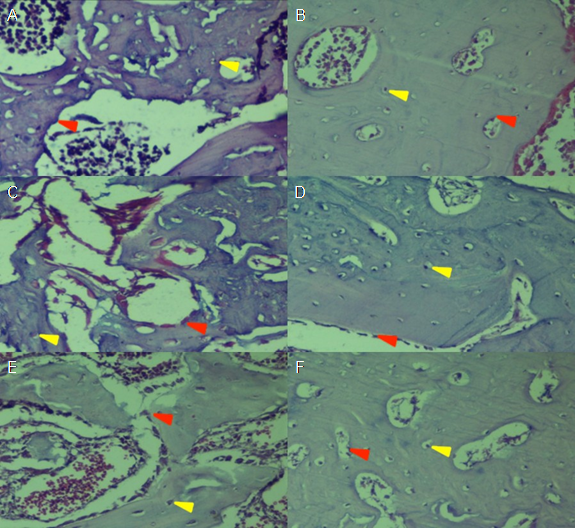

Figure 1 shows the histological process of bone repair at 14 days and 30 days after surgery. It is observed that osteoblasts and immature forms of bone trabeculae predominate at 15 days (Figure 1. A, C and E); on the other hand, osteocytes and better bone organization become more evident at 30 days (Figure 1. B, D, F).